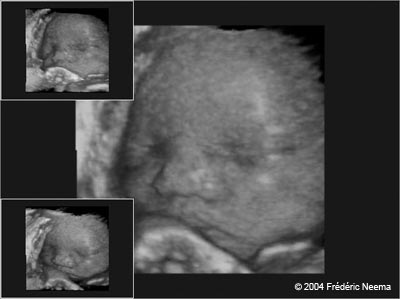

The 3-D image of an unborn child revealed by an ultrasound scan operated at the Prenatal Peek studio in Novato,CA. Expecting mothers can now have a glimpse of what their developing child might look like by going to private studios that offer 3D ultrasound imagery. Relaxing in recliners, with soft music playing in the background, mothers and their families have a chance to meet their babies and walk out with a video or DVD of their experience as well as color photographs. Unlike the classic 2D ultrasound performed by obstetricians to verify the absence of abnormalities, the 3D ultrasounds have no medical value.